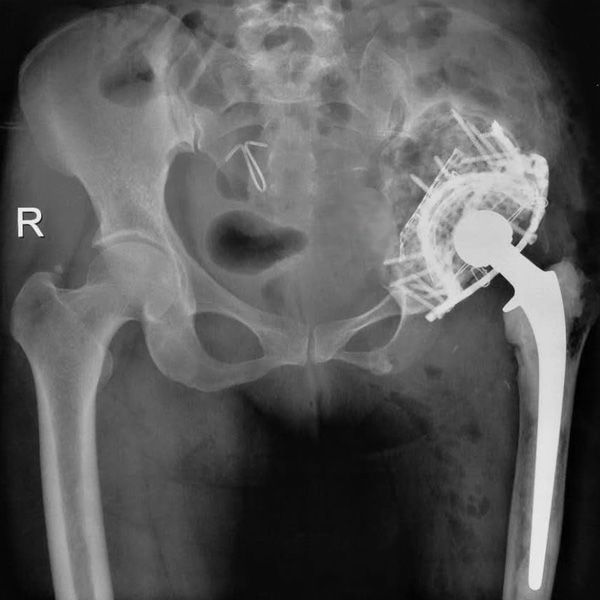

• 髖關節翻修髖關節翻修手術后手術前

髖關節翻修

患者蘇某,女性,11年前因“左髖關節屈曲攣縮畸形”行左側人工全髖關節置換,近來感覺左髖關節疼痛,不敢行走,經“攜生醫療平臺”就診于哈......

在線咨詢+更多詳情+